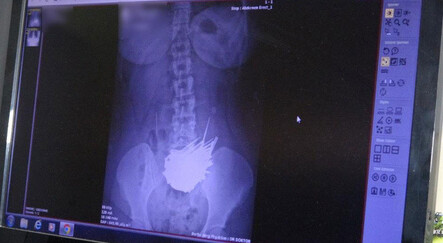

Omuz eklemi kolumuzun her yöne kolay hareket etmesini sağlar. Vücudumuzdaki en esnek eklem de olan omuz eklemi hem karmaşık bir yapıya sahiptir hem de esnekliği nedeniyle zedelenmelere ve sakatlanmalara çok açıktır. Omuz bölgesinde oluşan travmalar ağrılara yol açabilir. Bazen buradaki kas gelişimindeki zayıflıklar omuz ekleminin çıkmasına da sebep olabilir.

Omuz ağrısı genellikle kemikleri çevreleyen ve hareket kabiliyetini oluşturan yumuşak doku zedelenmeleriyle ortaya çıkar. Omuz sıkışma sendromu ise bazen kolun baş seviyesinin üzerine kaldırılmasıyla yapılan uzanma hareketiyle oluşur. Omuz ekleminden kaynaklı ağrıların yanısıra vücudun farklı bölgelerindeki sorunların buraya yansımasıyla da omuz ağrısı hissedilebilir. Dolaşım bozuklukları, omuz sinirlerindeki iltihaplanma, kalp ve akciğer sorunları, boyun fıtığı, diyabet gibi bazı faktörler de omuz ağrısına yol açabilir.